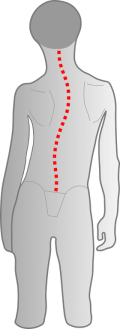

Fehlerhafte Informationen aus den verschobenen Gleichgewichtsorganen bzw. dem Nackenrezeptorenfeld beeinflussen die Verarbeitung im Gehirn und können zu einer Fehlhaltung der Wirbelsäule führen.

Dadurch wird der Kopf intuitiv schief gehalten, der Körpersinn entwickelt sich nicht richtig, was Auswirkungen auf die motorische Entwicklung und Körperwahrnehmung nach sich zieht.

Stimmt die Passung der obersten Wirbel nicht, kann dies zu einer Verkrümmung der Wirbelsäule führen.